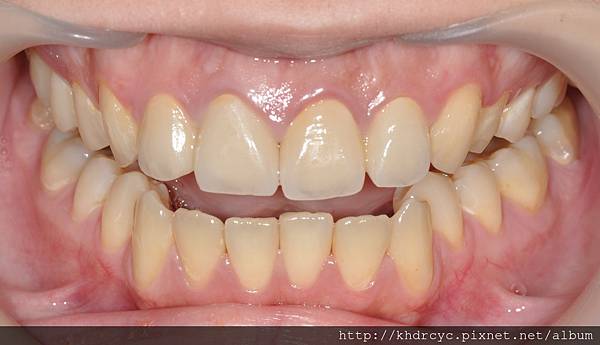

療程持續幫助仁武的C小姐蛀牙填補

與製作全瓷貼片繼續改善美觀

感謝仁武的C小姐對療程相當配合

欣美牙醫在短時間內達成任務

不但牙齒變美變白連口氣都改善了

笑起來也更能自信的露牙齒

唱歌也不用顧忌